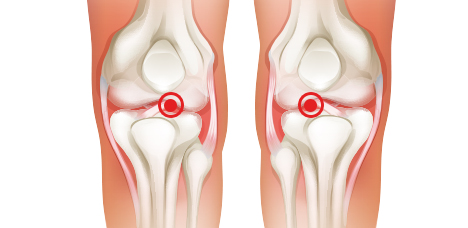

무릎 관절염

슬개골연화증, 관절염 등으로 인해 통증이 발생